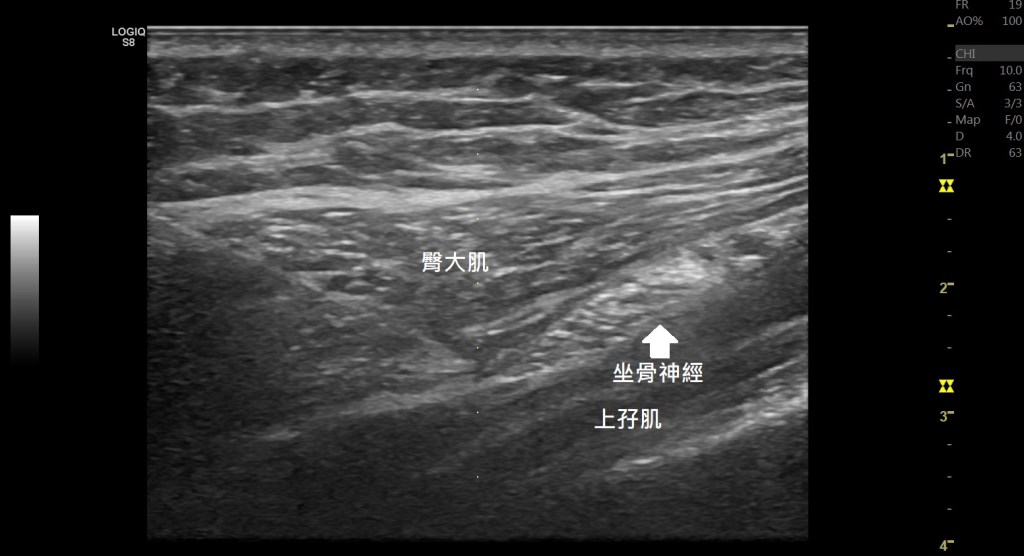

首先我們來看到在臀部後側的肌肉,除了梨狀肌之外,下側的上孖肌(gemellus superior)、閉孔內肌(obturator internus)、下孖肌(gemellus inferior)、股方肌(quadratus femoris)在髖關節為0度的時候,股骨的內轉也會拉緊。另外臀中肌的後側纖維(Gluteus medius, posterior fiber)也是。

這些都可以在動態超音波底下去區分壓迫到的位置與原因。